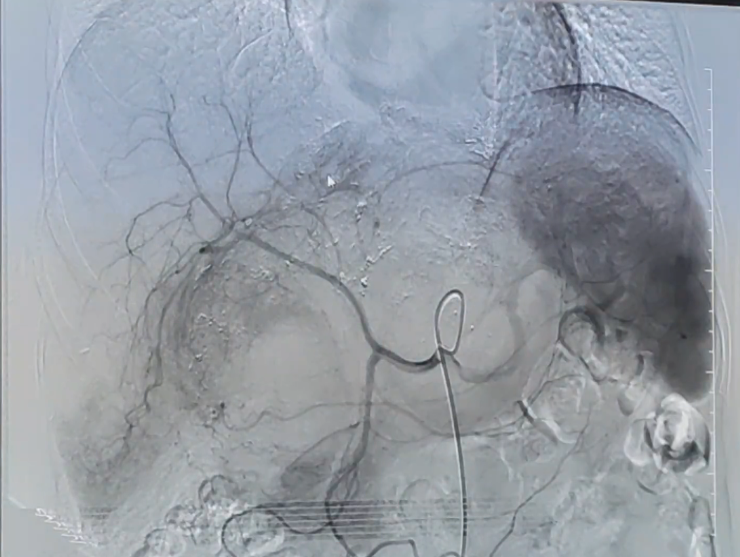

术中,DSA造影显示肿瘤血供丰富,且肿瘤已经侵犯到肝脏。介入科副主任杨清峰根据结果分析肿瘤主要血供来源为肝动脉的可能性比较大,遂在DSA引导下超选了肝左动脉、肝中动脉、肝右动脉三条主要供血动脉用栓塞剂将其阻塞,并经皮股动脉穿刺进行肝动脉、肠系膜上动脉灌注化疗术,在堵塞肿瘤成长所需营养供应的同时,杀伤并“饿死”肿瘤细胞。